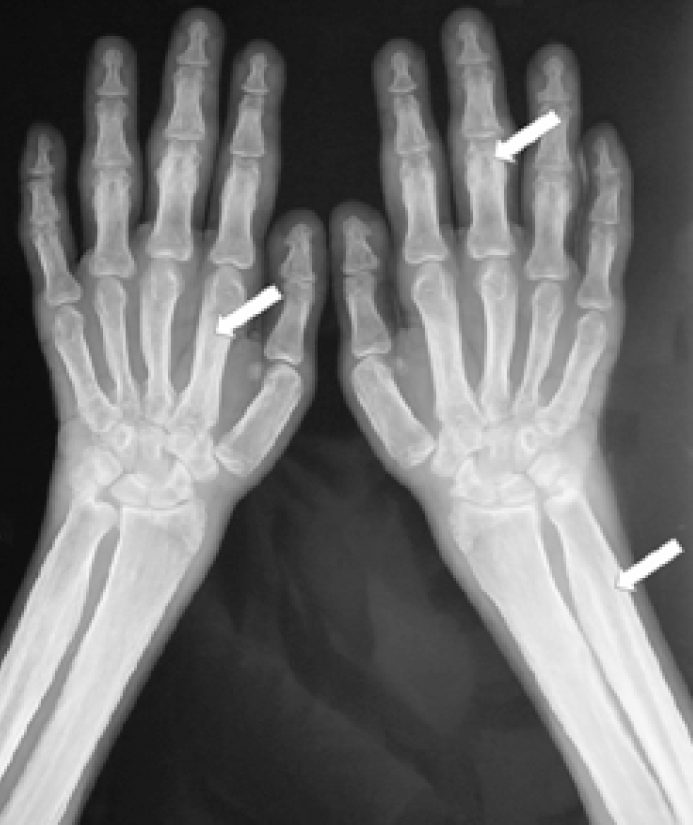

Pachydermoperiostosis (PHO) or primary hypertrophic osteoarthropathy is a rare genetic disease that typically begins during childhood or adolescence. It is characterized by digital clubbing, pachydermia and periosteal reaction and progresses gradually over the years prior to disease stabilization. Two genes are reported to be associated with PHO – HPGD and SLCO2A1. These genes are involved in prostaglandin E2 metabolism.

We present a description of a 19-year-old patient with PHO. We found two mutations in the SLCO2A1 gene: p.Gly183Ar (chr3:133673888, NM_005630.2:c.547G>A) and p.Cys444Gly (chr3:133664070, NM_005630.2:c.1330T>G) through molecular genetic analysis. The mutation (p.Cys444Gly) has never been recorded in previous studies.